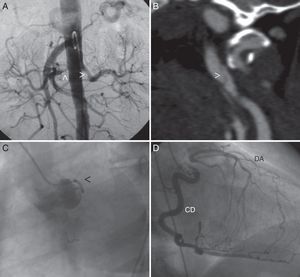

Presentamos una mujer de 43 años de edad, con antecedentes de hipertensión arterial sistémica secundaria a estenosis bilateral de las arterias renales (fig. 1A) y accidente cerebral isquémico por disección de la arteria carótida izquierda (fig. 1B) que es enviada para valoración por angina de esfuerzo. La coronariografía mostró la oclusión proximal de la descendente anterior (fig. 1C) con flujo colateral desde la coronaria derecha (fig. 1D). La aortografía de troncos supraaórticos fue normal. No se evidenciaron datos de anemia, trombocitopenia, alteraciones en los reactantes de fase aguda ni de la autoinmunidad.

A) Aortografía abdominal evidenciando estenosis proximal a nivel de ambas arterias renales (punta de flecha). B) Angiografía por tomografía computarizada donde se observa disección de la arteria carótida izquierda (punta de flecha). C) Coronariografía izquierda (oblicua anterior izquierda) donde únicamente se ve una arteria circunfleja de escaso desarrollo (punta de la flecha). D) Coronariografía derecha (oblicua anterior derecha) donde se evidencia una coronaria derecha (CD) dominante que rellena por circulación colateral de la descendente anterior (DA), que se encuentra ocluida a nivel proximal.